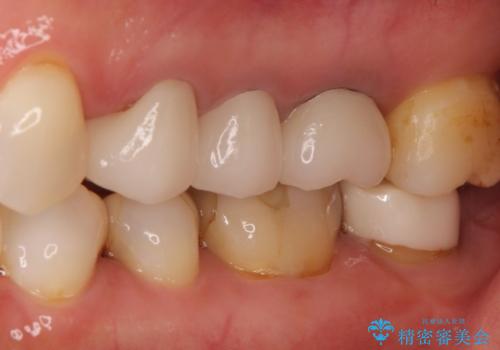

【オールセラミッククラウン】プラスチックの被せ物が壊れた。

- 以前他院で治療した被せ物が壊れたことを主訴に来院されました。

強度に優れたオールセラミッククラウンにて治療を行なっております。

3歯同時に治療を行うこと来院回数は4回で終了しています。